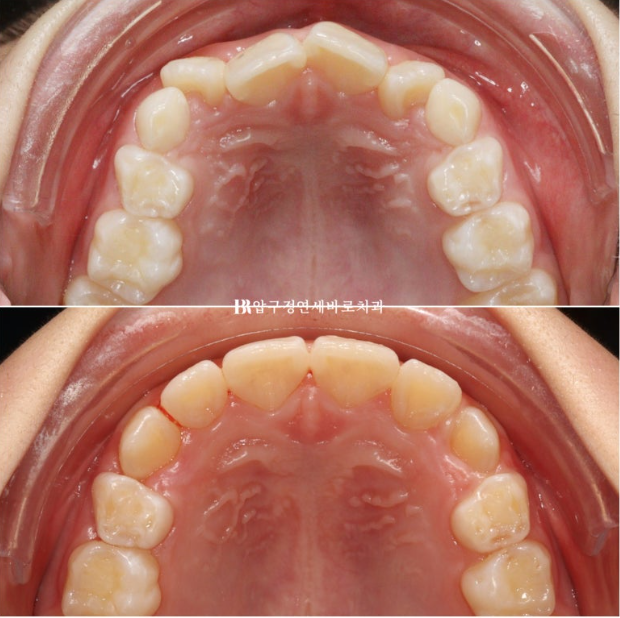

2022.11~2024.06

첫장치는 43개였고 두번째는 17개였으니 총 60개의 장치 5일씩 착용했던 아이니까 300일의 총 치료기간입니다.

그리 길지 않은 기간이지만 치료계획이 적절하고 장치만 잘 껴준다면 인비절라인 퍼스트로 소아교정을 했을 때 결과가 아주 좋습니다.

미리 충분하게 만들어놓은 공간으로 송곳니 등 후속 영구치들이 맹출하고 있습니다.

영구치가 적절한 수준까지 올라오면 고정식 유지장치까지 해줄 계획입니다.

이 친구는 아마 영구치열에 2차 교정이 따로 필요 없을 것 같습니다.